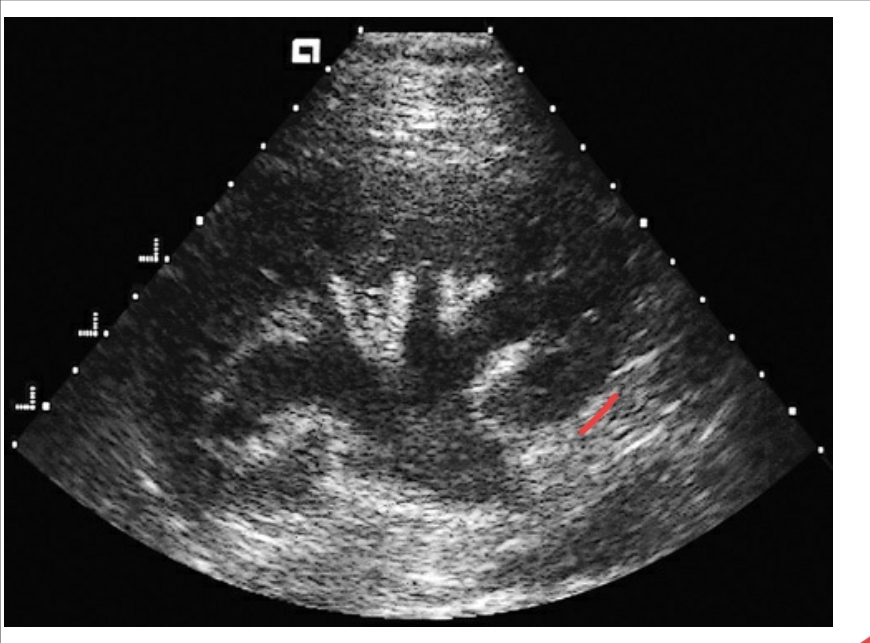

Which of the following conditions is most likely demonstrated in this sonogram of the kidney?

1. Pelviectasis

2. Pyelonephritis

3. Nephrolithiasis

4. Hydronephrosis

A

1. Hydronephrosis

The most common etiology for this pathology is

1. Bladder infection

2. Kidney infection

3. Urinary stasis

4. Urinary tract obstruction

d. Urinary tract obstruction

The arrow in this sonogram most likely identifies: 1. Perinephric fat 2. A renal abscess 3. Pyelnephritis 4. Thrombosis in the IVC

1, Perinephric fat